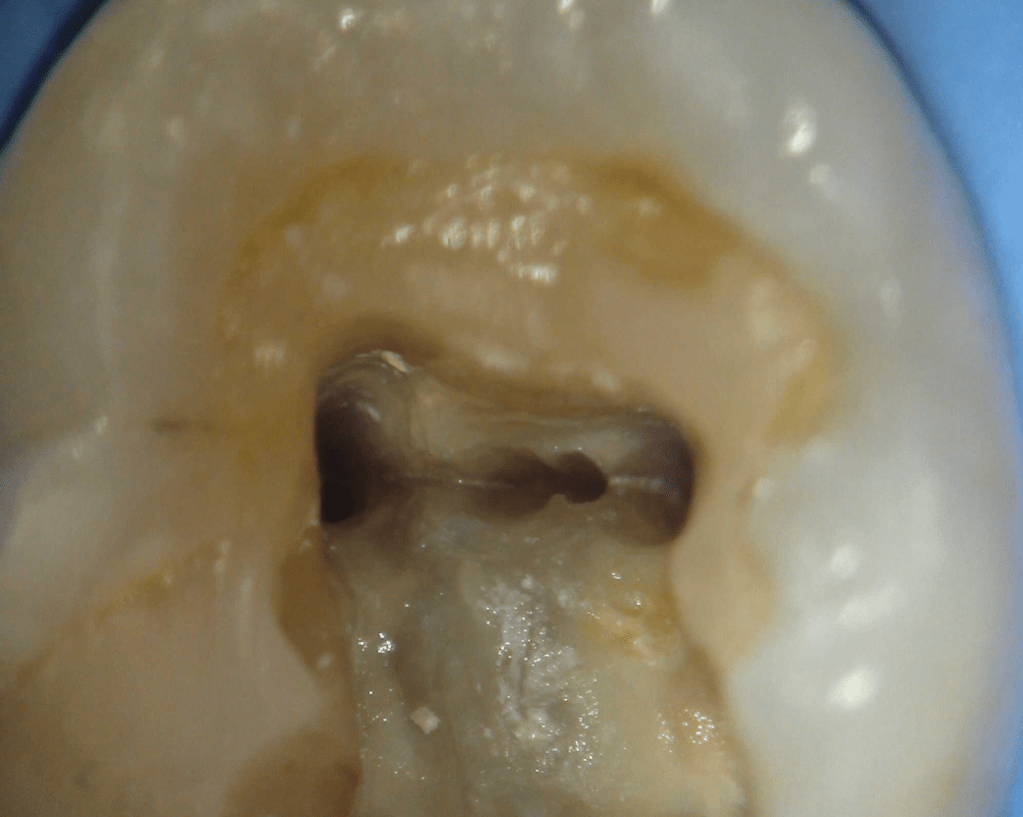

Pulpotomía biodentine + reco preendio